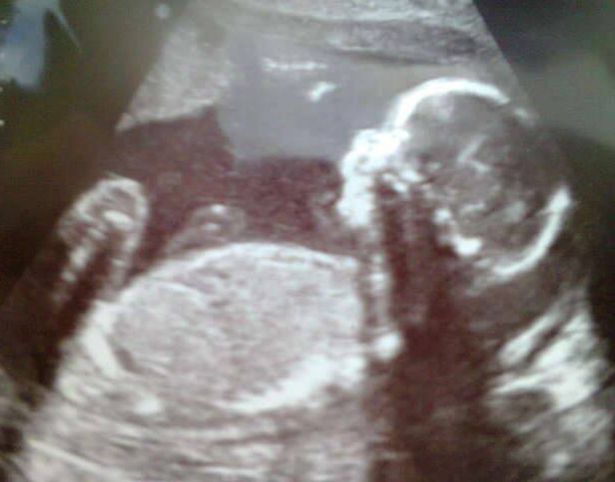

GALLES – Amy Poole, una madre di 22 anni, alla 22esima settimana di gravidanza ha scoperto che qualcosa non andava nel bambino. I medici hanno infatti detto che il piccolo aveva un tessuto morbido che gli cresceva sulla faccia. Quando Ollie è nato, sua madre era senza parole: “Quando mi hanno dato Ollie, era così sorpresa che non riuscivo a parlare. Era così piccolo, ma aveva un rigonfiamento grande quando una palla da golf sul naso”. Il bambino è infatti affetto dall’encefalopatia, una malattia generativa del cervello che porta ad una moltitudine di sintomi. Nel caso di Ollie, un buco nel cranio ha lasciato che una parte del cervello finisse nel naso, che ora presenta un’enorme protuberanza.